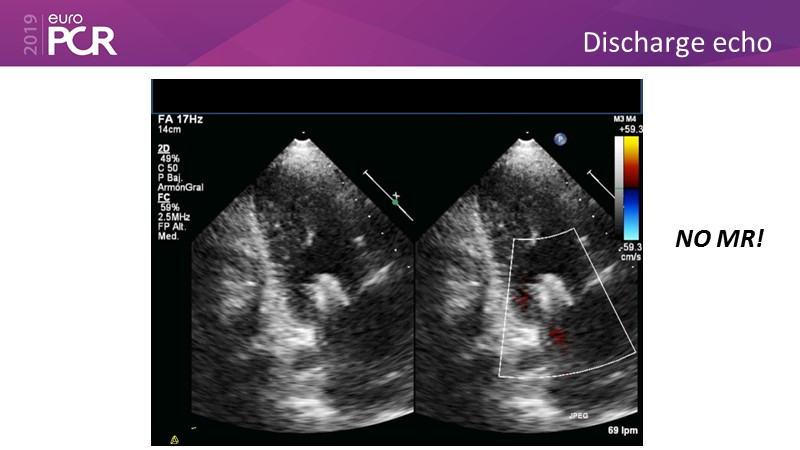

- To learn how will product innovation (Mitraclip NTR / XTR) drive improvement in procedural and clinical outcomes (EXPAND)